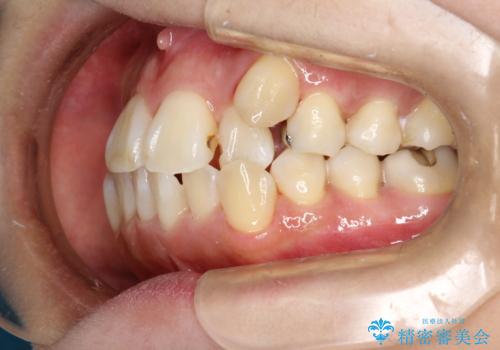

- これから矯正治療を始めるため、今の状態でも歯をきれいにしておきたいとのことでした。PMTC60分コースを行いました。

プラーク(細菌の塊)や歯石がたまると歯の表面はザラつきいてきます。そのザラつきは歯周病や虫歯菌の棲家となります。そのまま放置すると、歯肉が腫れてきたり、歯肉から出血したり、口臭が強くでたりします。とくに歯肉の境目は、歯磨きで汚れを除去することが難しく、プラーク(細菌の塊)や歯石が溜まりやすい場所です。

歯並が、がたついている場合はなおさら汚れが溜まりやすいです。矯正治療前や矯正中、定期的にPMTCをすることで、矯正治療中の歯肉トラブルを防ぐことにつながります。